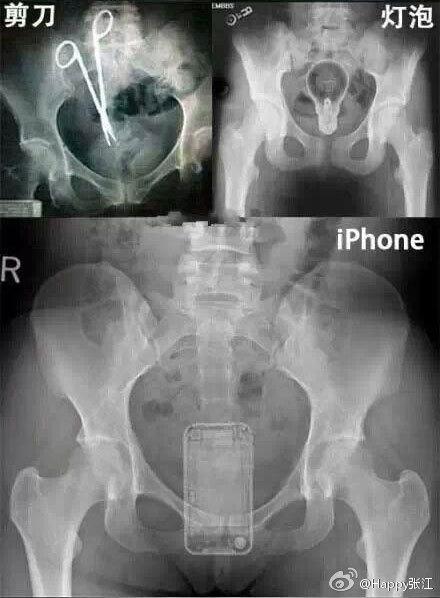

据说这是医生们盘点的肛门塞入东西的奇葩之最,毁三观啊